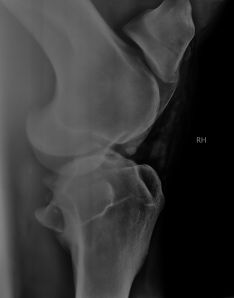

But let me start at the beginning. On 16th July, Nazir had an arthroscopy to remove two cartilage fragments in his right stifle joint (see this blog post). The surgeon, Dr Jan Samsel of the clinic at he Warsaw race track, found and removed the two pieces and proudly told me that it was quite difficult to find one of them, that it had grown into surrounding tissue, but that he’d managed. Nazir walked out of the wake-up box all right. The x-ray on the right was taken during surgery, after the removal of the two chips.

Then, a few hours after the surgery, his joint started swelling a lot and he showed signs of extreme pain. He was standing on three legs. The surgery was minimal invasive, so this was not normal and the surgeon said that it was the first time something like that had happened in his entire career. To all our dismay, the x-ray now showed another large fragment. The surgeon was just as worried as I was.